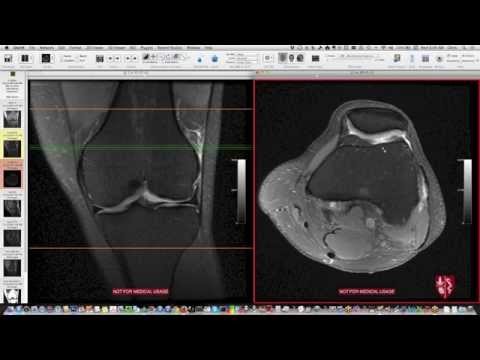

Систематическая интерпретация МРТ коленного сустава: как я это делаю

Эффективный обзор МРТ коленного сустава. Больше случаев можно найти в видео части II и на сайте (используйте Chrome или Firefox). От заведующего отделением радиологии опорно-двигательного аппарата Стэнфордского университета.